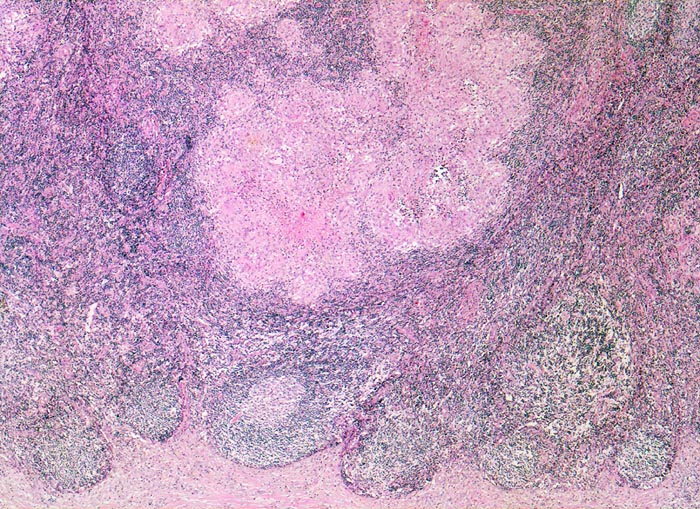

PathoPic – image database / PathoPic ID 4254 - retikulozytär-abszedierende Lymphadenitis bei Katzenkratzkrankheit

retikulozytär-abszedierende Lymphadenitis bei Katzenkratzkrankheit

Lymphknoten, Axilla

Unten im Bild die fibrosierte Lymphknotenkapsel. In der angrenzenden Rinde mehrere Lymphfollikel, eines davon mit Keimzentrum. Oben im Bild konfluierende histiozytäre Granulome mit zentraler Nekrose.

Nachweis von kleinen pleomorphen Bakterien

Druckschmerzhafte Lymphknotenvergrösserung in der rechten Axilla 2 Wochen nachdem der Patient von seiner Katze an der rechten Hand gekratzt wurde.

Keine käsige Nekrose wie bei Tbc.